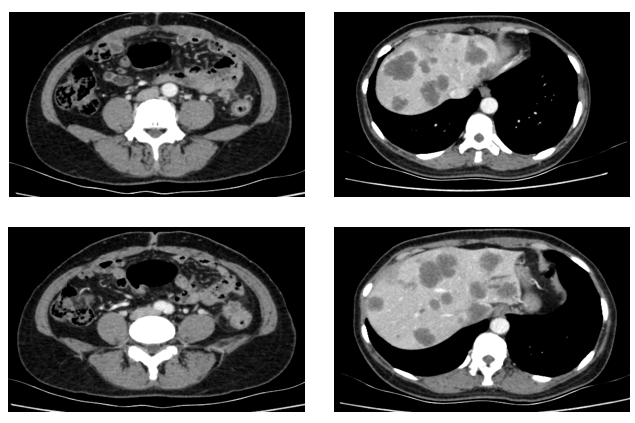

于2021.04.17行“FOLFOX6”方案化疗1周期,行“奥沙利铂”化疗时,出现严重过敏。因患者基因状态为RAS,BRAF野生型,第2周期始给予“FOLFIRI+西妥昔单抗”,在治疗过程中,肿瘤标志物持续下降,影像学也显示肝脏病灶明显缩小。疗效评价PR,在2021-09-25在局麻DSA下行“肝动脉造影并化疗灌注栓塞术”。

患者于2021年11月30号复查时,肺上病灶增大增多,肝脏病灶稍增大,肿瘤标志物增高,整体疗效评价PD,考虑一线治疗进展。